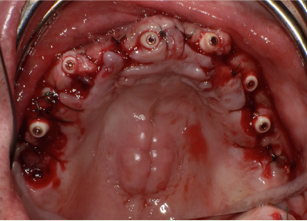

中途半端に悪い歯を残すと、後々治療が大変になるので思い切ってすべての歯を抜歯します

術直後の写真です

オールオン6本のインプラントをいれました

初期固定もよかったので即時荷重をおこなっています

術後2週間 傷もきれいに治ってきています